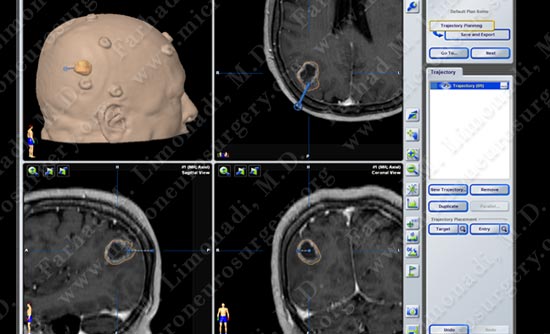

Surgical Procedure

- She underwent surgical resection of this tumor utilizing brain mapping, stereotactic and computer navigation, and intra-operative neurophysiological monitoring.

Stereotactic and computer navigation was used to determine the precise location of the tumor (outlined in yellow).